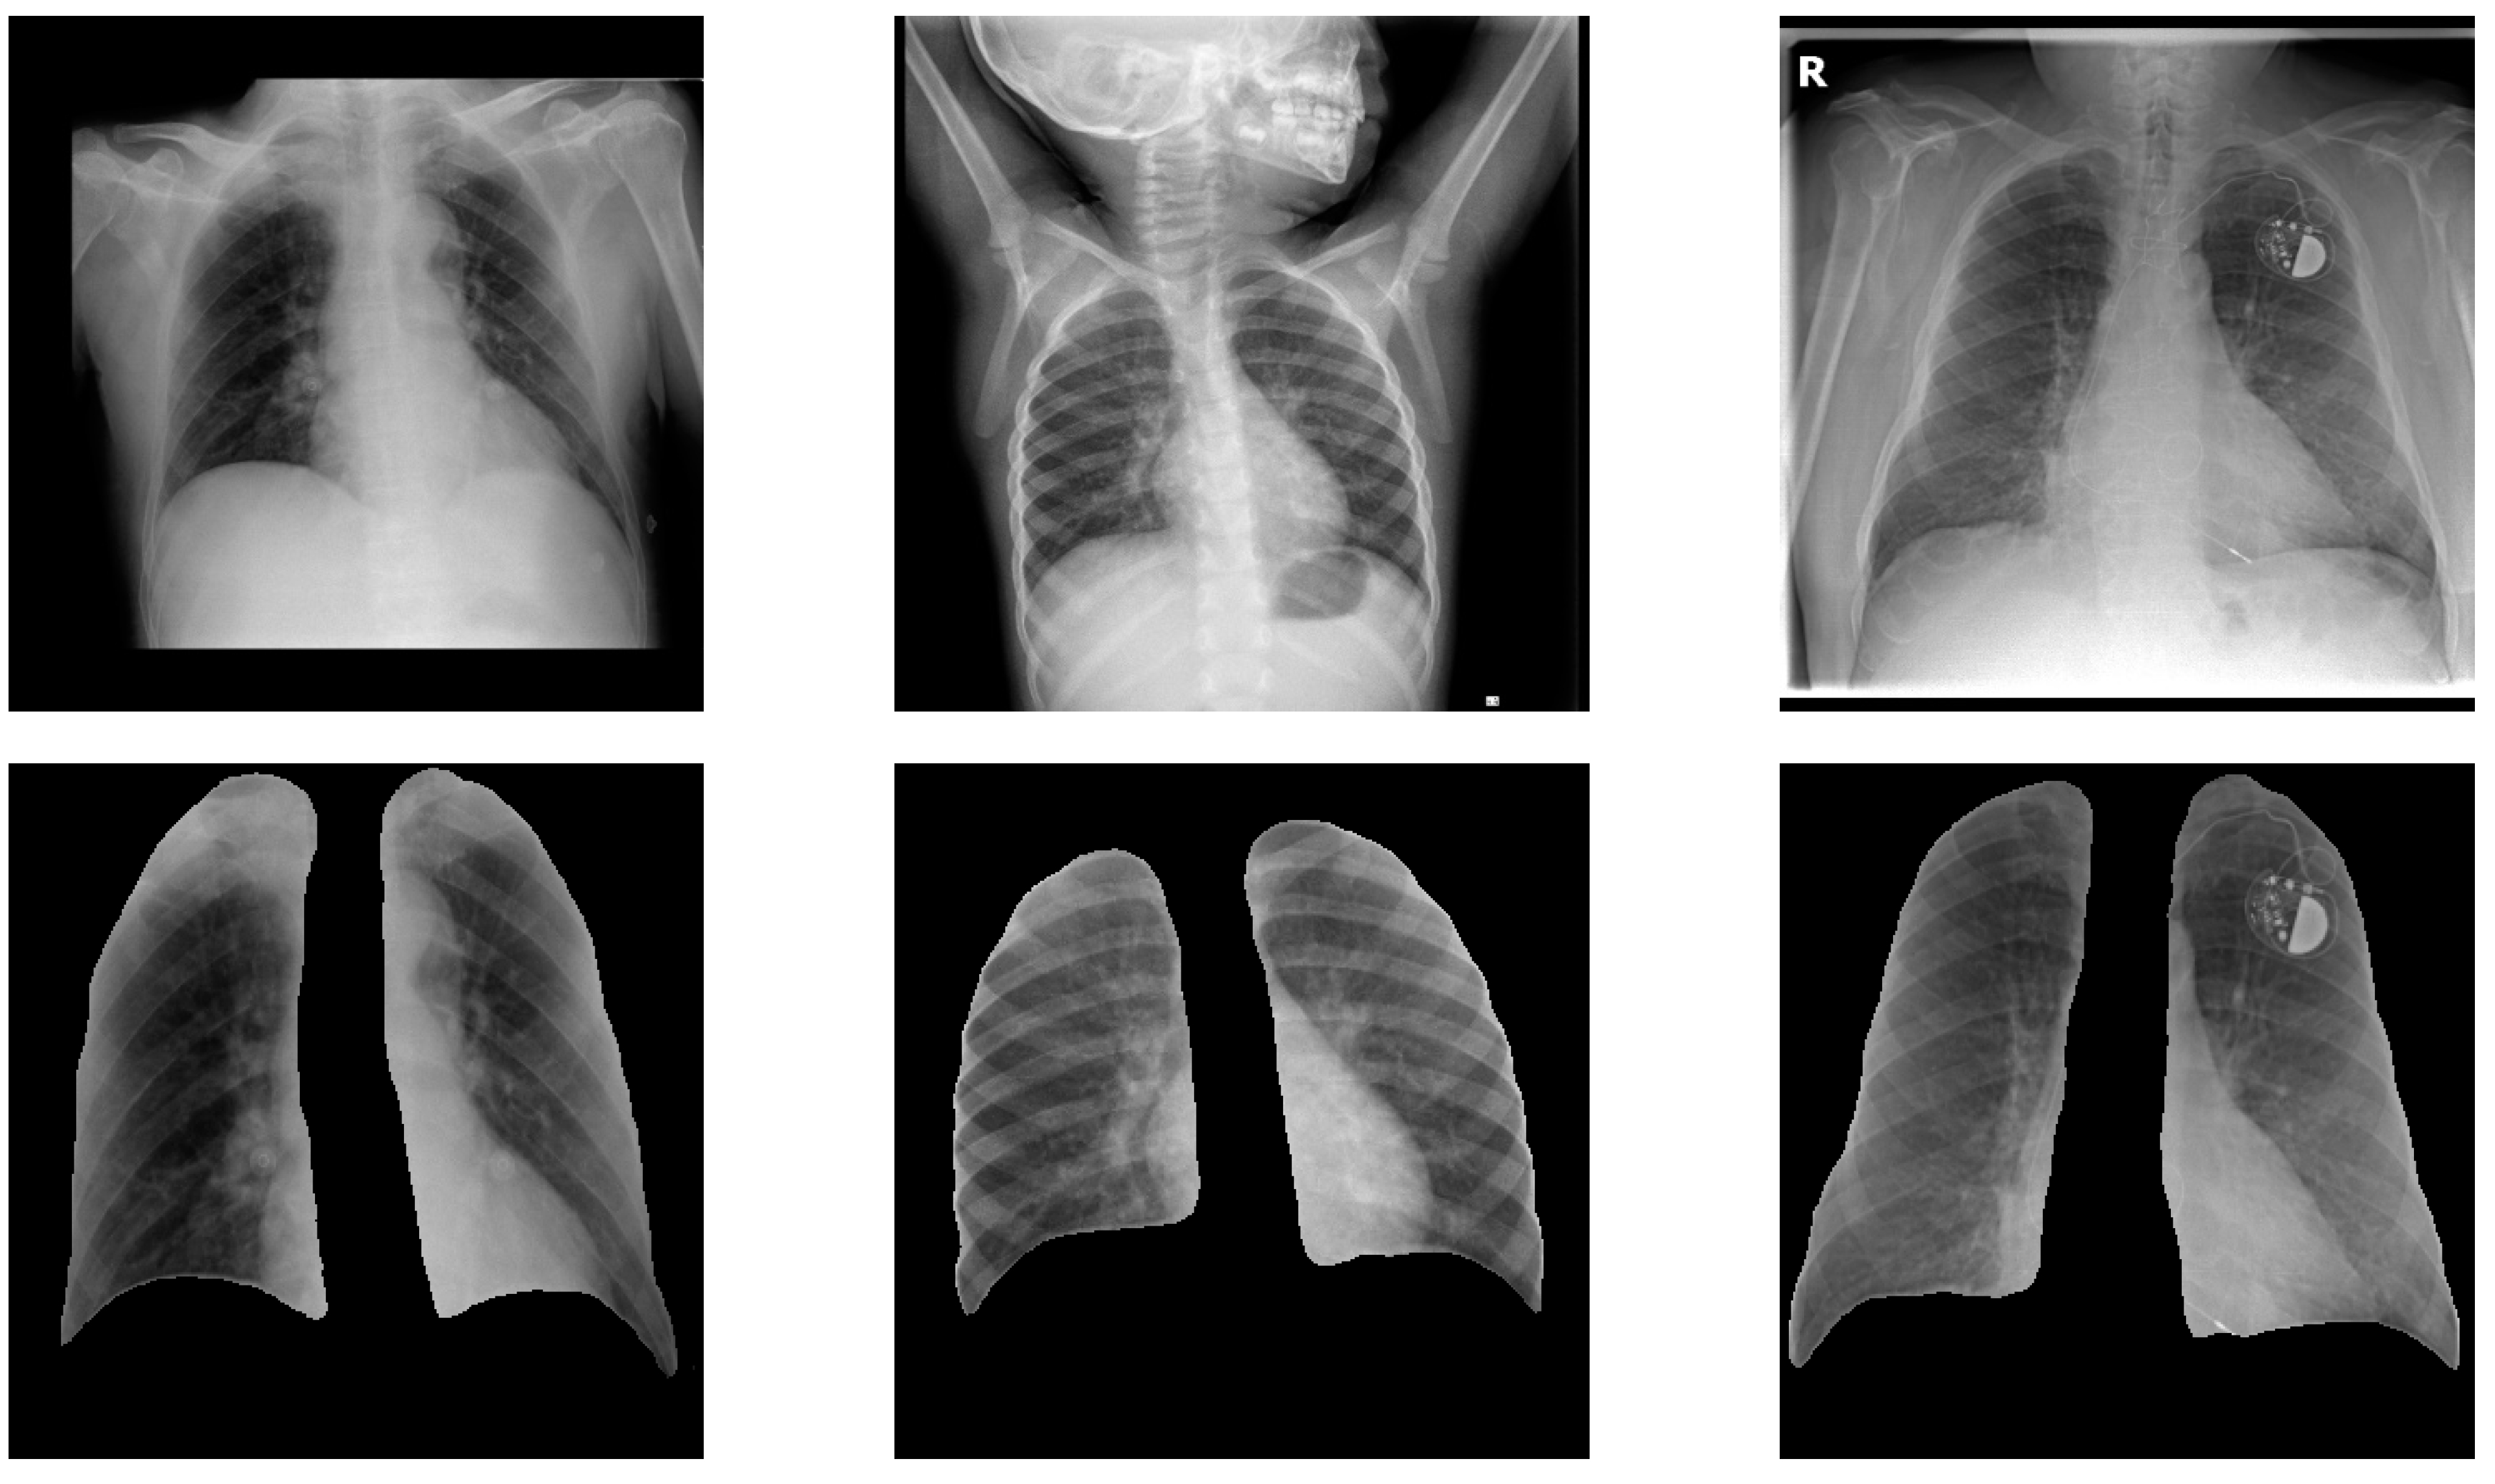

3.2.2. Lung Segmentation